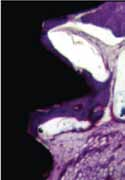

Titanul de grad 23 (Ti 6Al 4V ELI) este un material de mare succes pentru fabricarea implanturilor dentare, datorită combinației favorabile a proprietăților sale, cum ar fi greutatea netă scăzută, raportul înaltă rezistență la greutate, modulul de elasticitate ridicat, coroziunea foarte ridicată rezistență și o bună biocompatibilitate generală.

Capacitatea excelentă de biocompatibilitate și osseointegrare a titanului este legată de proprietățile materialului și de suprafața acestuia:

– O peliculă de oxid pasiv rezistent, foarte rezistent, care protejează metalul substrat de oxidare și coroziune.

– O rată de dizolvare foarte scăzută a filmului de oxid și o concentrație extrem de scăzută a titanului încărcat.